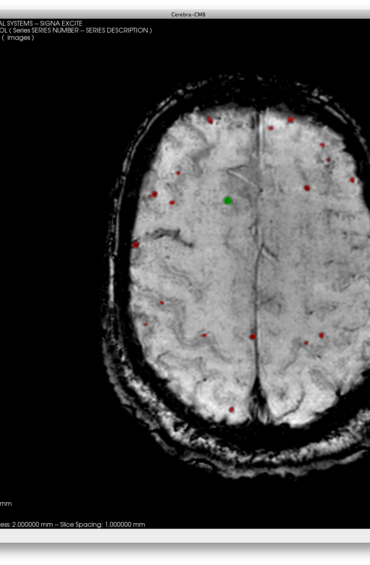

Cerebra-WML

Cerebra-WML is a stand-alone custom application developed to perform quantitative analysis of white matter lesions (WML), based on the assumption that these lesions present as white-matter hyper-intensities in T2-weighted magnetic resonance (MR) images. Cerebra-WML is designed to lead the user through a workflow to detect and quantify WMLs while allowing a rapid and consistent evaluation of the MR images.